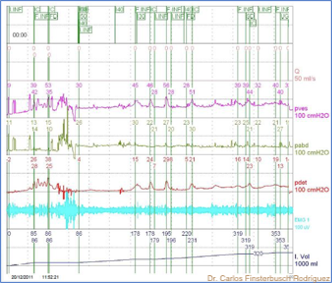

El trazo cistométrico graficado habitual tiene distintos canales que disponen simultáneamente presión vesical, presión abdominal y presión del detrusor, que es la presión efectivamente producida por la contacción del músculo detrusor y que se calcula por medio de la sustracción a la presión vesical de la presión abdominal (Pdet = Pves-Pabd), flujo urinario, volumen vaciado, residuo post miccional y por último electromiografía perineal.

Se observan reiterados aumentos de presión vesical (Pves) en ausencia de aumentos de presión abdominal (Pabd), lo que se refleja en la curva de Presión del detrusor (Pdet).

Hiperactividad terminal del detrusor

Al final de la fase de continencia se observa un aumento de presión vesical (Pves) en ausencia de aumento de presión abdominal (Pabd) que se refleja en la curva de Presión del detrusor (Pdet) y desencadena la micción, representada por la curva de flujo (Q).

Obstrucción del tracto de salida

Al final de la fase de continencia se da la orden de orinar (VD) observa un aumento de presión del detrusor (Pdet) con una cuerva de flujo (Q) baja magnitud y forma aplanada.

Hipoactividad del detrusor

Al final de la fase de continencia se da la orden de orinar y se observa un bajo flujo (Q) que no es posible de contrarrestar con una adecuada contracción del detrusor del detrusor (Pdet).